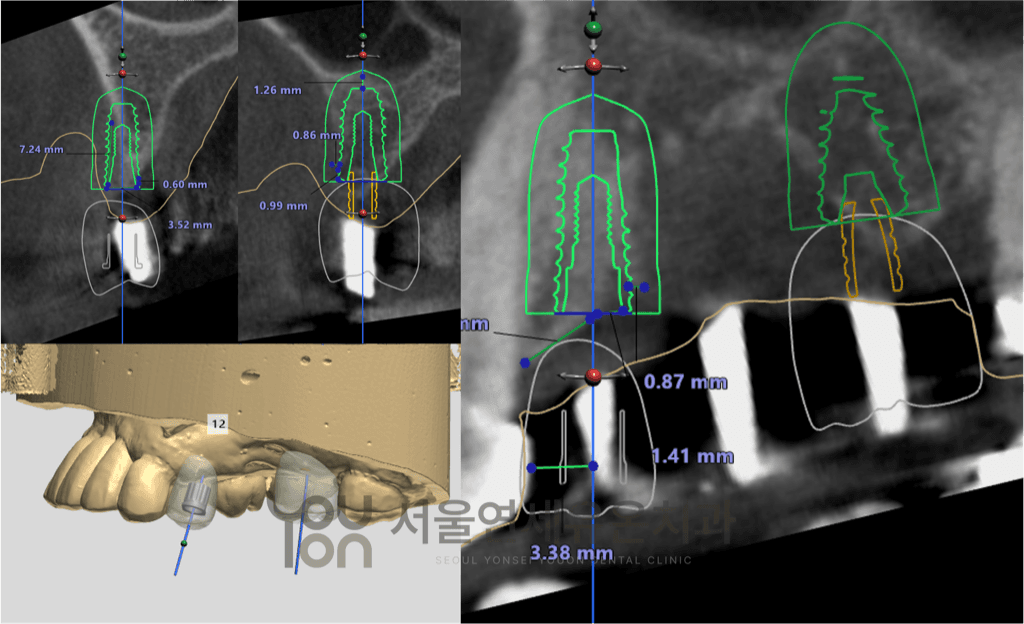

CT 정밀진단, 수술 가이드 등의 기술과

풍부한 수술 경험을 바탕으로

환자마다 다른 뼈와 잇몸 상태를 고려한

개인 맞춤형 임플란트 계획을 세웁니다.